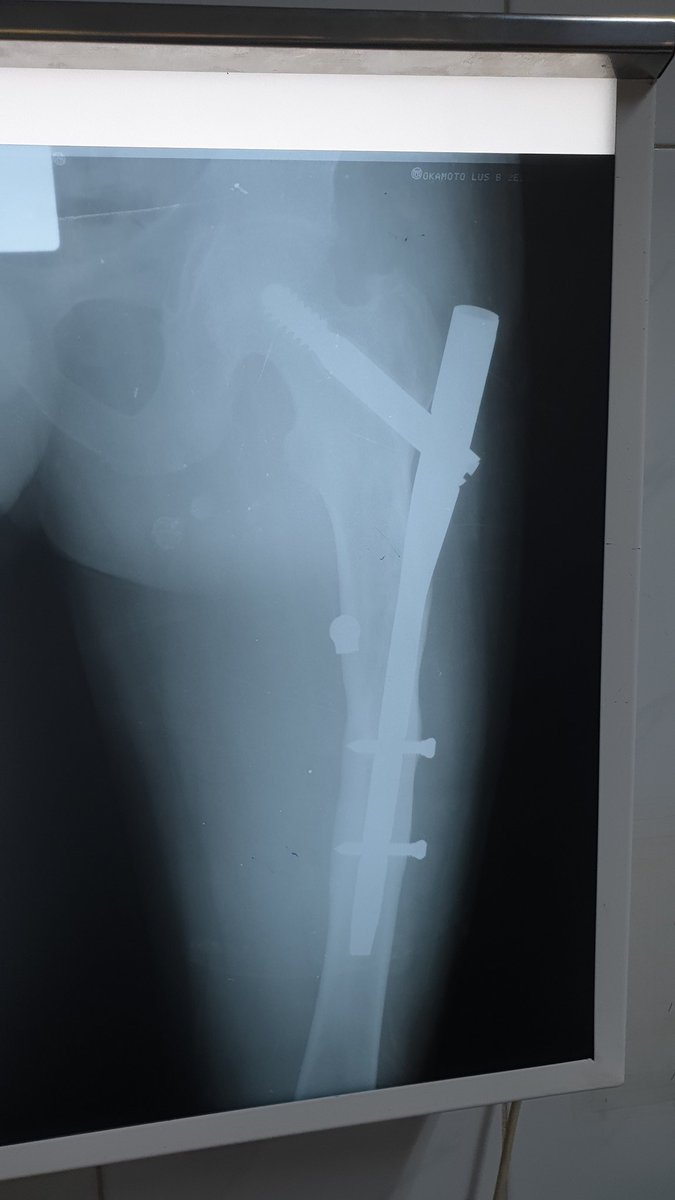

#OurWomanMentors arranca en Madrid el evento de #community dirigido al #liderazgo en traumatología. Coaching y magia para seguir creciendo. @AO_spain

Traumatology & https://t.co/mnYM2D4KUJ